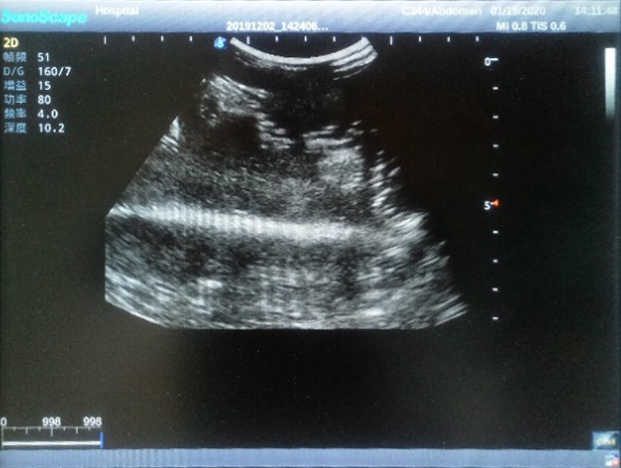

2)  Each model contains 8 space-occupying lesions of varying sizes, different in touch, elasticity and ultrasonogram

4) Biomimetic material allowing users to see clear and real normal tissues and space-occupying lesions that are hyperechoic, hypoechoic and isoechoic as they would see in the clinical environment